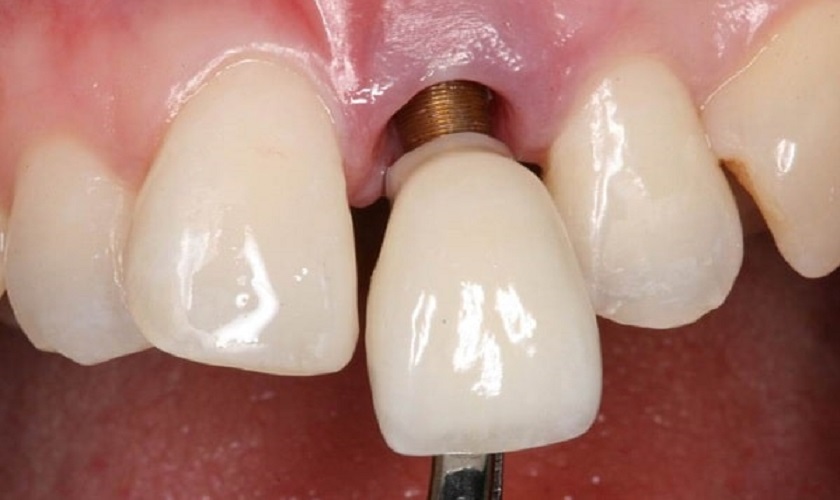

Cơ chế thành công của cấy ghép Implant là quá trình tích hợp xương. Khi đặt trụ Implant vào xương hàm, các tế bào tạo xương (hay còn gọi là tiền tạo cốt bào, tế bào xương non) sẽ di chuyển đến, trú ngụ trên bề mặt Implant và tạo ra mối liên kết sinh học vững chắc giữa xương và Implant. Chìa khóa của sự tích hợp này nằm ở khả năng tạo tế bào xương non của xương hàm.

Khi cấy Implant, các tiền tạo cốt bào không được sản sinh đủ, dẫn đến quá trình tích hợp xương thất bại, chân Implant không thể dính vào xương, gây ra hiện tượng mất tích hợp.